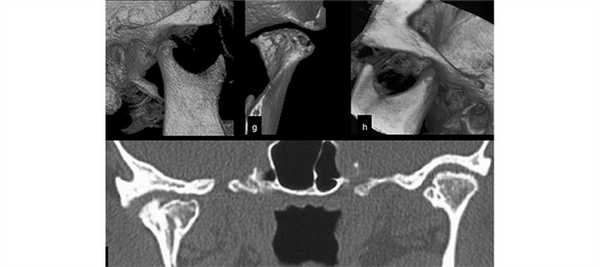

КТ ВНЧС - что показывает обследование?

При проведении КТ, предполагаемая патология или дефект становятся хорошо видны на мониторе компьютера. Изображение может быть получено в нескольких проекциях - аксиальной, фронтальной или сагиттальной.

Полученный снимок может определить следующие виды отклонений:

- Изменение размеров суставной щели.

- Отклонения суставного диска.

- Изменение костных структур.

- Наличие новообразований.

- Смещение головок сустава.

Разновидности обследования

КТ ВНЧС может проводиться с закрытым и открытым ртом, в зависимости от конкретного клинического случая. Во время проведения процедуры могут использоваться различные варианты этого обследования:

- Траснаксиальная методика. Это стандартная процедура (через ось тела). В ходе ее проведения получается порядка 25 снимков, идущих параллельно глазной ямке. Можно визуализировать отдельно левый и правый сустав.

- Саггитальное сканирование. Оно проводится строго параллельно ушной раковине. Ведется оценка состояния ВНЧС в трех фазах, т.е. пациента просят закрыть рот, приоткрыть его наполовину и полностью.

- Объемный 3D-режим. Получается пространственное изображение правого и левого сустава.

Благодаря сканированию в аксиальной проекции, КТ височно-нижнечелюстных суставов позволяет воссоздать форму костных суставных поверхностей, оценить состояние сочленения и прилегающих тканей.

КТ височно-нижнечелюстных суставов в трех взаимно перпендикулярных проекциях дает возможность воссоздать достоверную 3D-модель, где будут отражены малейшие изменения суставных элементов, свидетельствующие о развивающихся патологических процессах.